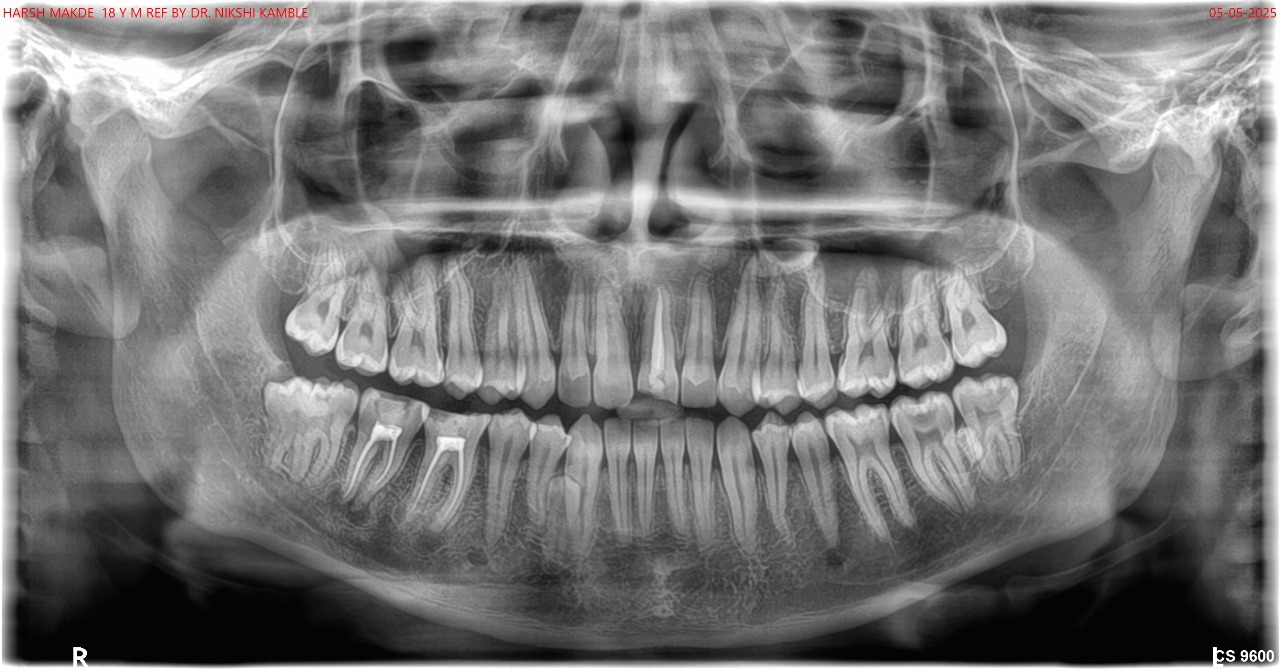

Provides a broad view of the entire jaw, useful for orthodontic planning.

Dental X-rays, also called radiographs, are images of your teeth, bones, and jaw structures captured using controlled, low doses of radiation. They help detect hidden issues such as decay between teeth, bone loss, abscesses, and impacted teeth that aren’t visible during a routine check-up. Dentists also use X-rays to assess growth, position of unerupted teeth, and readiness for treatment like braces or dental implants.

At Dr. Nikshis Orthodontic Centre and Dental Implant Clinic, we utilize cutting-edge digital radiography to capture high-resolution images of your teeth, bone, and supporting structures. This advanced technology ensures that we identify hidden dental issues early, providing a “people-first” approach that prioritizes your safety and long-term oral health.